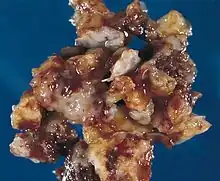

A cardiac myxoma is a noncancerous tumor of the heart that may embolise and grow at the site of embolisation.[1] Symptoms depend on the tumor size, location, shape, mobility and how fast it grows.[1] More than two-thirds have severe symptoms such as heart failure, stroke and embolisation.[3] Up to a fifth may have no symptoms.[1] Typical presentations include shortness of breath, feeling faint, chest pain, palpitations, fever, weight loss and joint pains.[1] There may be sudden death.[1]

Although any chamber may be affected, most arise within the left atrium near the valve of the fossa ovalis.[1] It may run in families as part of Carney syndrome, or may occur sporadically.[2] The tumor is derived from multipotent mesenchymal cells.[4]

The surgery is treatment of choice,[13] tumor must be surgically removed. Some patients will also need their mitral valve replaced. This can be done during the same surgery. Usually, inadequate excision of the tumor, development from a secondary focus, or intracardiac implantation from the primary tumor are the attributable explanation for recurrence,[14] and it is more likely to occur in the first 10 postoperative years, especially in younger patients.[15]

Although a myxoma is not malignant with risk of metastasis,[6] complications are common. Untreated, a myxoma can lead to an embolism (tumor cells breaking off and traveling with the bloodstream). Myxoma fragments can move to the brain, eye, or limbs.